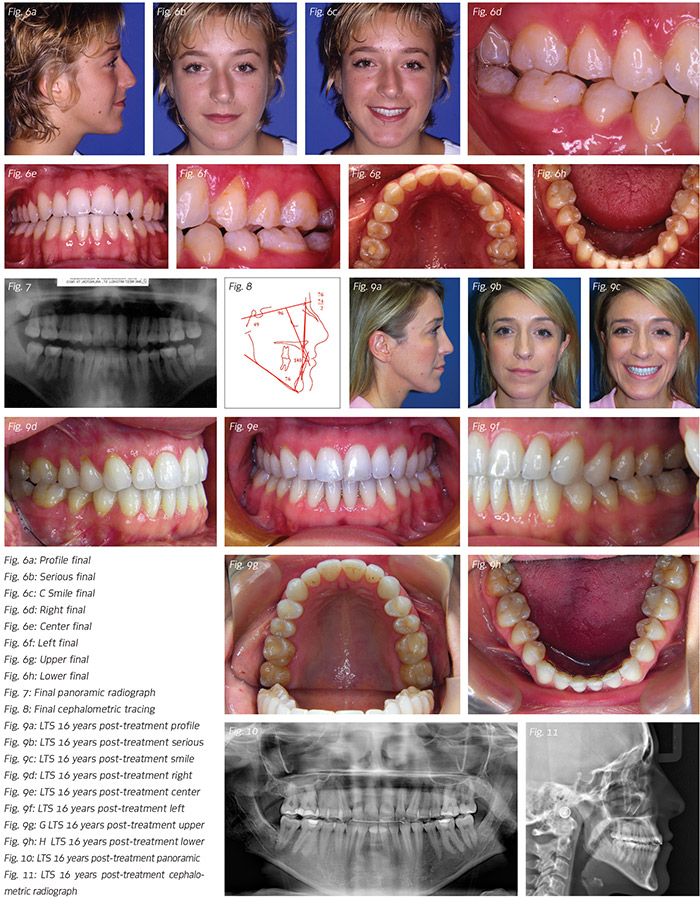

Although a conscientious practitioner can learn much from every case treated, certain patients can stand out and be unusually educated when they display unique conditions and then respond to treatment in manners not expected. Such a patient is presented here, a 16-year-old female with an extremely high angle, Class III skeletal pattern. Dentally, she was Class III molar relationship, right posterior crossbite, anterior open bite of four millimeters. She had a mandibular arch length discrepancy of five millimeters.

The patient had an extremely vertical skeletal pattern (SN–MP of 49 degrees), a transversely constricted maxilla, a dental open bite (four millimeters) and a tongue thrust. Skeletal surgery (three piece maxilla) was discussed but we agreed to attempt treating the patient non-surgically and non-extraction.

Long-term Stability

Open bite malocclusions are difficult enough to maintain stability, but when adding Class III non-growing skeletal patterns, the challenge is even greater. Sixteen years post treatment, the patient continues with her “tongue exercises” and sleeps with a wrap-around retainer with a small hole in the anterior part of the acrylic where she places her tongue.1

Interestingly, the occlusion improved with time! Why? My assumption is that the final occlusion is in stable position with the oral and intra-oral muscular tissues functioning normally.

1. At her request, she continues to wear the bonded 3x3. This is common in most adult patients.